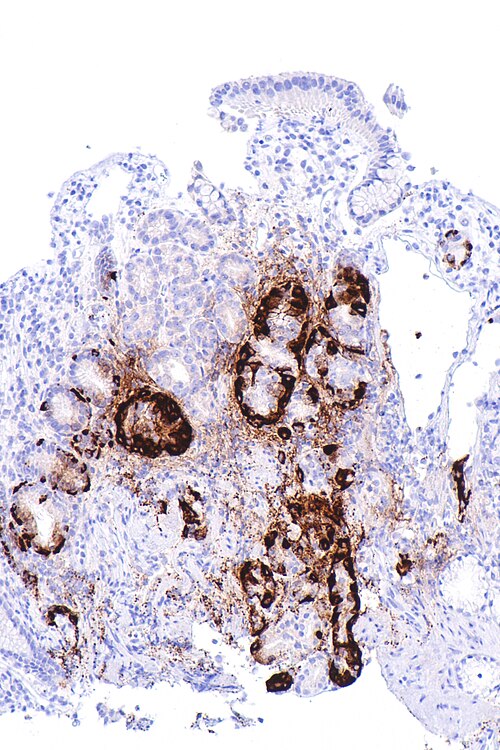

Nephron · CC BY-SA 4.0 · source

Diagnostic evaluation begins with complete blood count and peripheral smear demonstrating macrocytosis and hypersegmented neutrophils; such hematologic criteria are standard in protocols from European Society of Hematology and American Society of Hematology. Serum cobalamin measurement, methylmalonic acid and homocysteine assays follow, with assay validation studies published by laboratories affiliated with Centers for Disease Control and Prevention and National Institutes of Health. Detection of anti-intrinsic factor and anti-parietal cell antibodies aids diagnosis; immunological assay methods are refined in laboratories at Mount Sinai Hospital and MRC Laboratory of Molecular Biology. Historically, the Schilling test was used and is documented in archives at institutions like Guy's Hospital and University College London, but it is now rarely performed. Endoscopic evaluation with gastric biopsy to document autoimmune gastritis and exclude malignancy is guided by gastroenterology guidelines from American College of Gastroenterology and studies from Karolinska University Hospital.